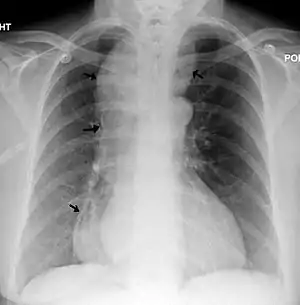

| Chest x-ray of an individual with achalasia. The arrows point to the areas of extreme esophageal dilation. | |

| Symptoms | Manifestation of achalasia: regurgitation, vomiting and dysphagia, alongside diagnosis of microcephaly: abnormally small head size below the third percentile as well as mild to moderate mental retardation. |